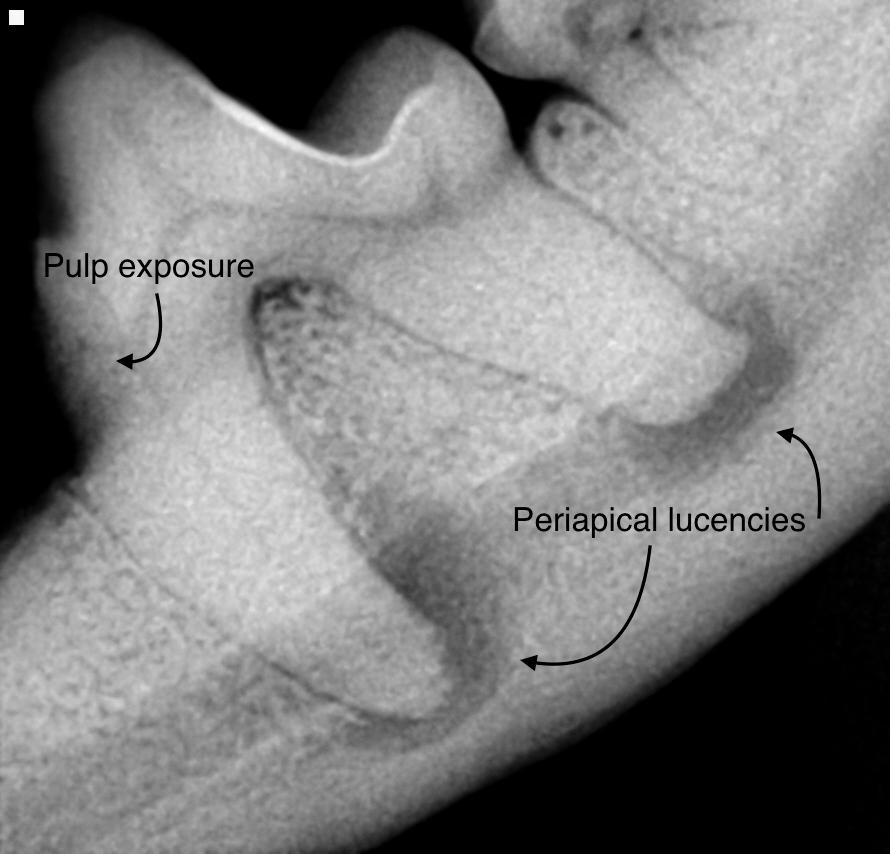

• Periapical pathology, such as widened periodontal ligament space at the tooth's apex and circumscribed alveolar bone resorption. In the early stages of endodontic disease, bony changes are not radiographically present. As the infection progresses, a homogeneous radiolucency at the apex or a dark halo in the periapical tissues becomes apparent, typical of an infection. A sharply outlined circumscribed radiolucent area is commonly caused by a periapical cyst, which usually arises from preexisting granulomas.

Figure 6: Right maxillary second incisor enlarged root canal and periapical lucency consistent with endodontic disease. Image courtesy of Dr. Jan Bellows. Figure 7A: Fractured left mandibular canine with pulp exposure and periapical lucency. Figure 7B: Periapical lucencies surrounding the three roots of the right maxillary fourth premolar. Figure 7C: Pulp exposure and periapical lucencies consistent with apical granulomas affecting a dog’s left mandibular first molar. Image courtesy of Dr. Jan Bellows.